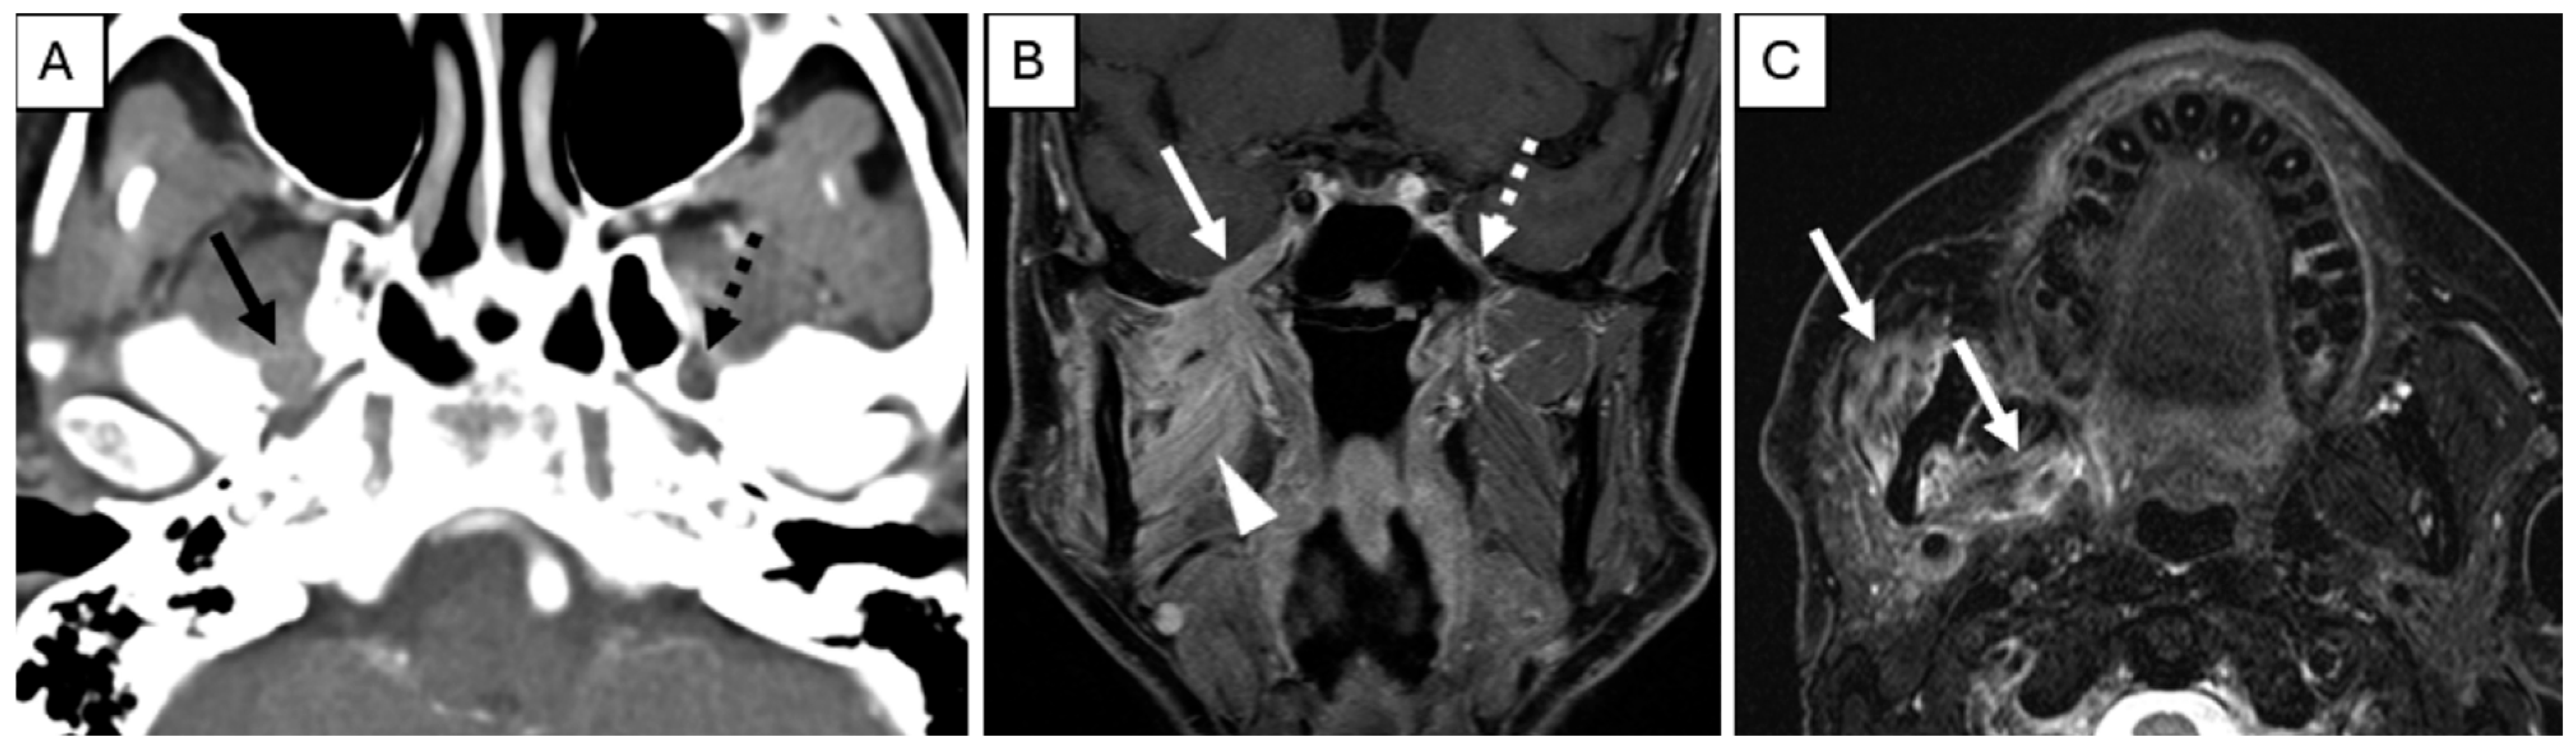

On imaging, PNI appears as abnormal thickening or enhancement of cranial nerves and their branches (which may be discontinuous), loss of normal perineural fat planes (most often seen at the foramina), and foraminal widening at key skull base locations, including foramen rotundum, foramen ovale, cavernous sinus, and Meckel’s cave (Figure 2) [43,44,45]. In advanced disease with cPNI or nodal involvement, fludeoxyglucose F18 positron emission tomography (FDG-PET) is valuable for assessing regional and distant metastases and may show linear or focal uptake along the involved cranial nerves or foramina [43]. Imaging is particularly recommended for high-risk cSCC, including BWH stage T2b/T3 tumors, PNI, and tumors located in anatomically complex regions (e.g., head and neck) where preoperative imaging can impact therapeutic planning. Retrospective studies suggest that baseline imaging of draining nodal basins in BWH stage T2b or higher tumors reveals abnormal findings in 59% to 65%, resulting in changes to clinical management in up to 33% of patients [1,46].

Figure 2.

Pre-treatment Examination: Perineural Tumor Spread. (A), Axial contrast-enhanced computed tomography of the skull base demonstrates loss of perineural fat and thickening of the mandibular division of the right trigeminal nerve (solid arrow). Note the preserved fat plane on the left (dashed arrow). (B), Coronal T1-weighted, fat-saturated postcontrast image demonstrates abnormal thickening and enhancement of the right mandibular division of the trigeminal nerve extending through the foramen ovale into the cavernous sinus (solid arrow). Note the normal left side (dashed arrow). Abnormal enhancement of the right masticator space muscles (arrowhead) is compatible with subacute denervation changes. (C), Axial T2-weighted image demonstrates hyperintense signal within the right muscles of mastication (arrows) compatible with subacute denervation changes, directing the search pattern to the mandibular division of the trigeminal nerve.